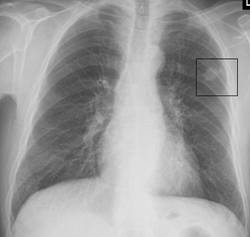

| Raio-X de pulmão com câncer. (Fonte Google). |

O pulmão é freqüentemente atingido pelo tabaco como mostra o RX ao lado. Aproximadamente 30% dos óbitos por câncer de pulmão são ocasionados pelo cigarro. Outras doenças respiratórias, tipo bronquites crônicas e enfisemas que podem preceder o câncer, são freqüentemente ocasionadas pelo tabaco. Nota-se que o pulmão não é o único órgão que se prejudica: cânceres do estômago e esôfago entre outros são favorecidos pelo tabagismo.